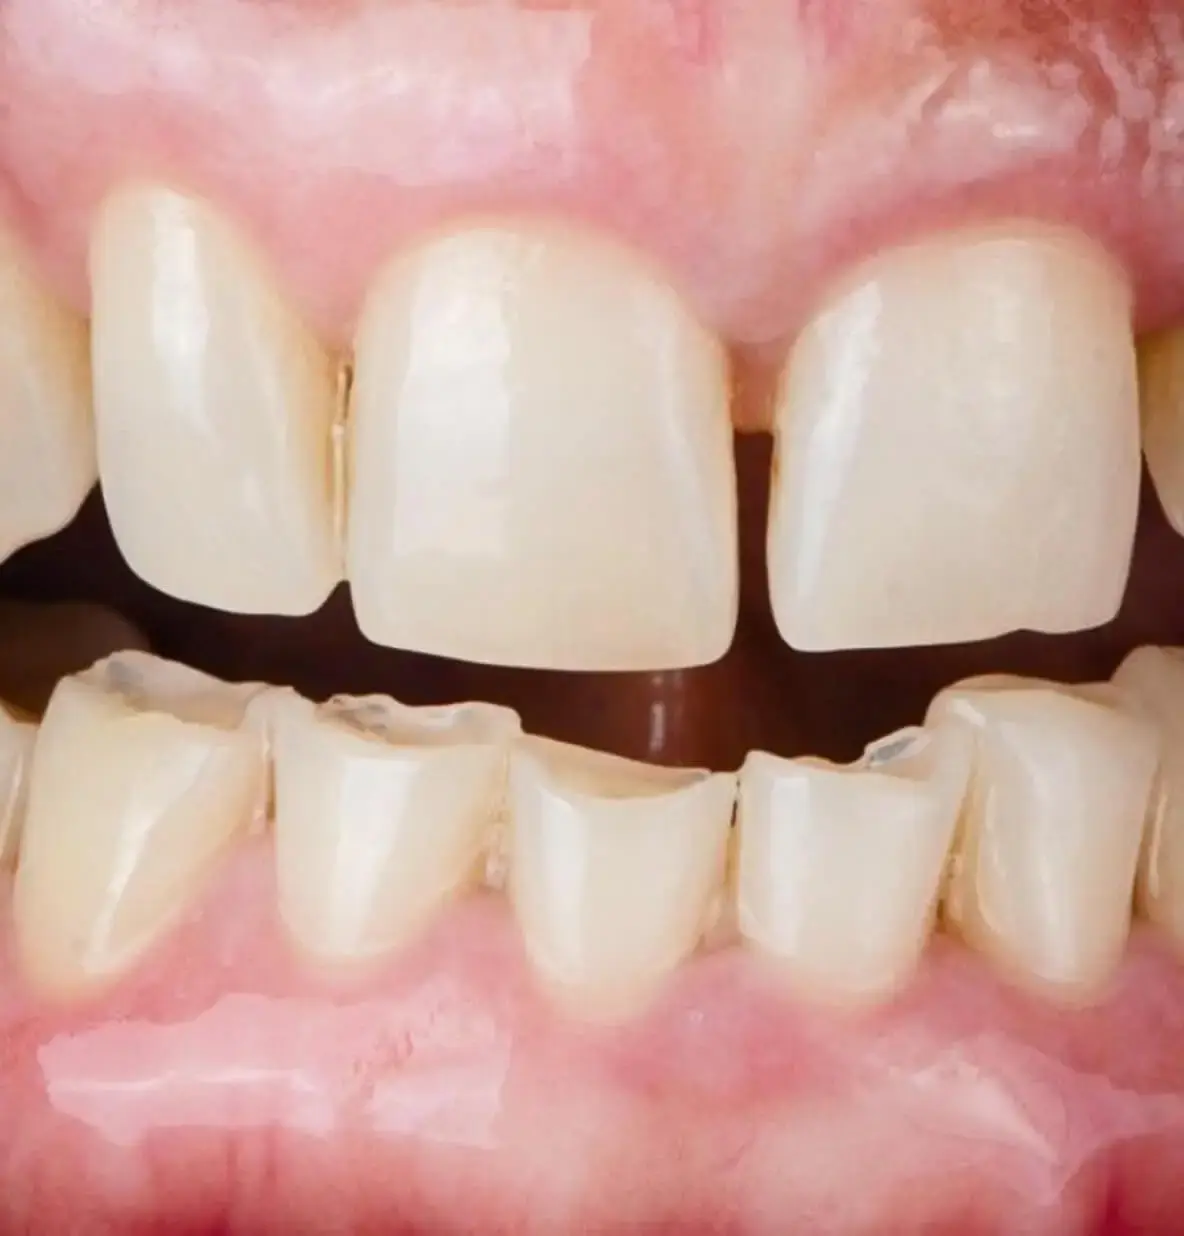

Глубокий прикус зубов — аномалия, при которой верхние резцы слишком (более чем на 1/3) перекрывают нижние при смыкании челюстей. В тяжелых случаях нижние зубы могут упираться в небо, травмируя слизистую оболочку и вызывая постоянный дискомфорт.

Симптомы глубокого прикуса у взрослых и детей видны при внешнем осмотре лица и в полости рта: укорочение нижней трети лица. Глубокое перекрытие, когда нижние резцы более чем наполовину скрыты под верхними. На внутренней стороне верхних зубов или десне нижних зубов снаружи видны следы от прикусывания. Изменение расположения подбородка из-за наличия дистальной или мезиальной окклюзии в сочетании с глубоким перекрытием. Выраженная надподбородочная складка.

Повышенная стираемость передних и боковых зубов является одним из серьезных последствий глубокого прикуса, поскольку неправильное смыкание зубных рядов усиливает нагрузку на эмаль и дентин, приводя к ускоренному износу твердых тканей зуба.